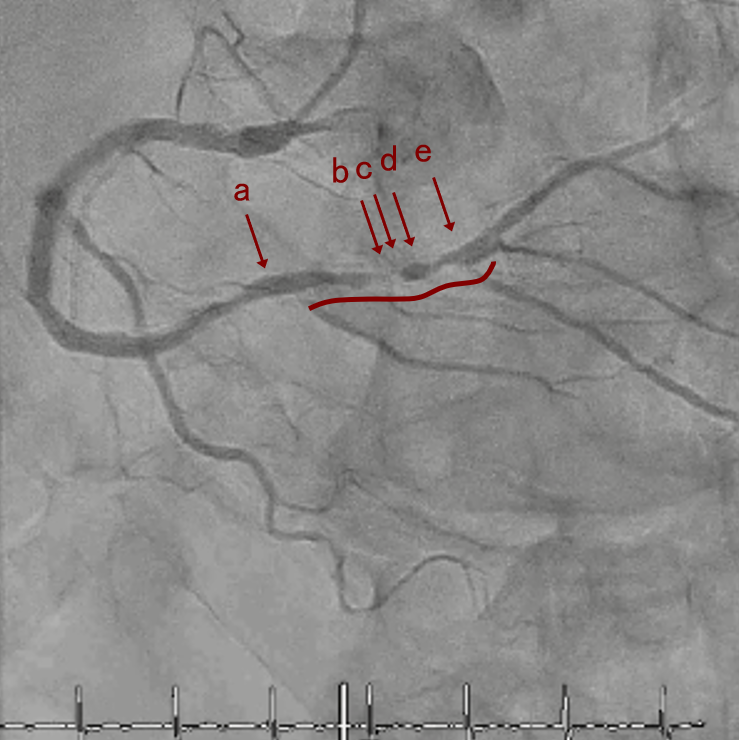

CAG

RCA distalの高度石灰化狭窄病変

IVUSでは8時方向からPD枝がはいいてくる。

PreのIVUSではaの部位のみlipid plaqueを認め削ることでdistal embolismのリスクがあり、そのほかは270度の偏心性石灰化であるがwire biasは良好。

OAS low speedによる引きを赤線の区間行う方針とした。